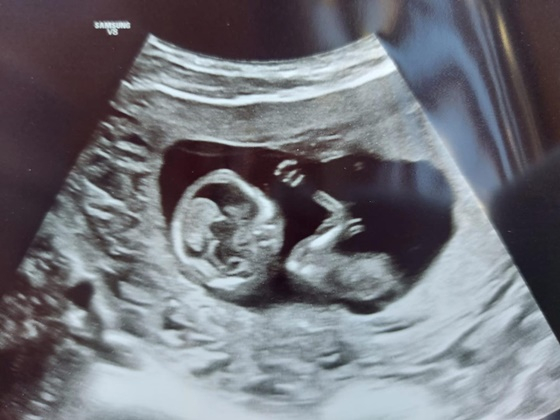

14일 빌푸는 "어제 핀란드는 아버지의 날이었다. 그런데 이제 저도 곧 아버지 역할을 하게 되었음을 알리게 돼 정말 기쁘다. 내년 3월에 저는 아들을 처음 만나게 된다"고 알렸다.